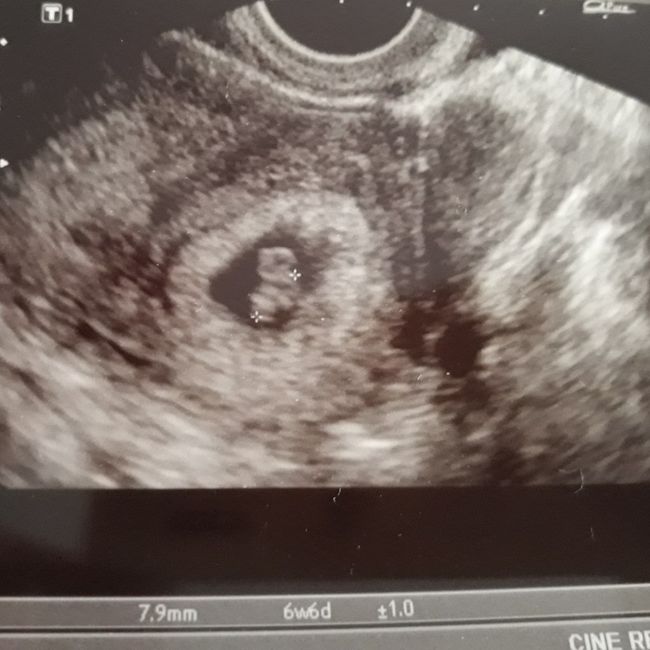

Io avevo fatto la prima eco a 6+6 e c'era tutto😍,però il battito si vedeva benissimo ma non l'avevamo sentito,per non disturbare il mio frugoletto😊

6+1 vuol dire 6 settimane e un giorno... Si comincia a contare dal primo giorno dell'ultima mestruazione... Nel tuo caso se non sai quando è stata di preciso ti diranno le settimane precise in base alla lunghezza dell'embrione... Il battito non si è sentito semplicemente perché non ha acceso il doppler perché può fare male quando sono così piccoli ma dall'eco si vedeva lo sfarfallio che è il cuore che batte e l'importante è vederlo appunto... L'eco è interna fino circa a 11/12 settimane perché finché l'utero non cresce un po' e non comincia a spostare gli organi che ha davanti con l'eco esterna si vede male...

A 6+1 visto tutto! Con embrioni di 2.2 mm... Ma i battiti ce li hanno fatti sentire verso le 11 settimane perché prima delle 10 settimane il doppler può dare noia...

Ciao a tutte, a quante settimane avete visto camera gestazionale e sentito il cuoricino? Io dovrei essere di 6/7 settimane, lunedì ho la prima eco ♥️♥️ Ansia 🤞🏻🤞🏻